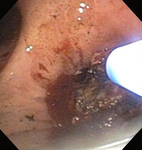

Стеноз дыхательных путей на фоне гранулематоза с полиангиитом (ранее именуемого гранулематозом Вегенера)

Из коллекций Хосе Фернандо Сантакруза, дипломированного врача, члена Американской коллегии специалистов в области торакальной медицины, DAABIP, и Эрика Фолка, дипломированного врача, магистра наук; используется с разрешения